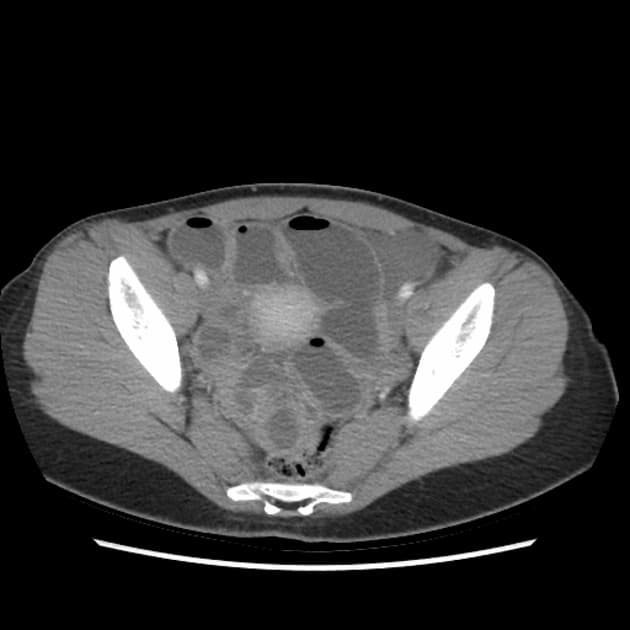

Biến dạng cấu trúc (architectural distortion) ruột kèm các đoạn hẹp (strictures) và các đường rò (fistulae) tại hố chậu phải, liên quan đến hồi cuối (terminal ileum). Cụ thể, phát hiện nhiều đường rò hồi – hồi (ileo-ileal) và hồi – đại tràng (ileocolonic), liên quan đến đại tràng lên và đại tràng xích-ma (sigmoid colon).

Hình ảnh tăng quang (hyperenhancement) và thành ruột non dày lên tại nửa bụng phải, cũng như tại đại tràng trực – xích-ma.

Có các đoạn hẹp (strictures) tại hồi tràng cuối và nhiều đường rò ruột – ruột (entero-enteric) và ruột – đại tràng (entero-colonic) tại hố chậu phải.

Có hiện tượng giãn đoạn trước hẹp (prestenotic dilatation) hồi tràng và đại tràng trực – xích-ma, mức độ thay đổi.